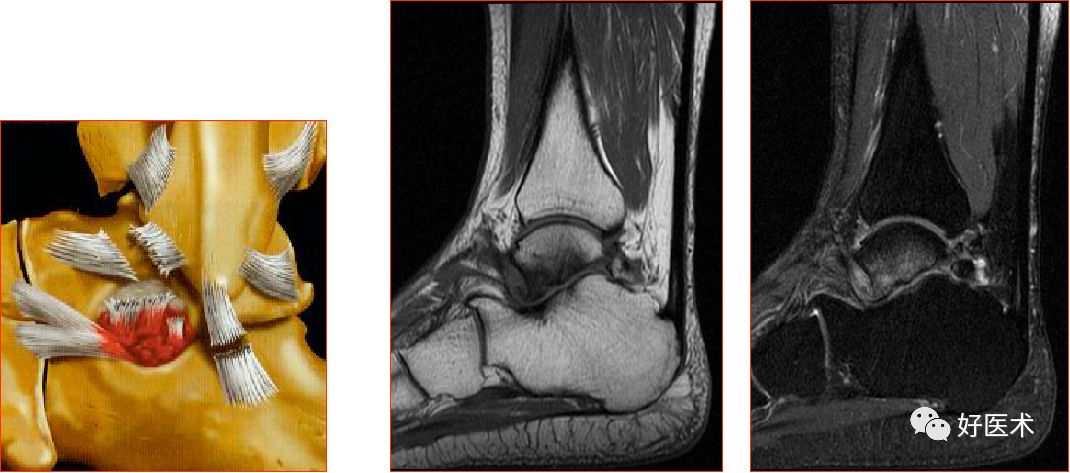

三角韧带

踝关节内侧韧带又称三角韧带,为强劲的三角形纤维束。上方附着于内踝尖及其前后缘;浅层纤维为胫舟部,前行附着于舟骨粗隆,部分与跟舟足底韧带的内侧面融合;中间部为胫跟部,下方附着于载距突;后部为胫距后部,纤维附着于至距骨内侧面和内侧结节。

三角韧带撕裂

三角骨综合征(距骨三角综合征)

足底腱膜炎(跖腱膜炎)

正常足底腱膜

足底腱膜炎MRI表现

足底腱膜炎:注意跟骨内侧结节的局限性水肿